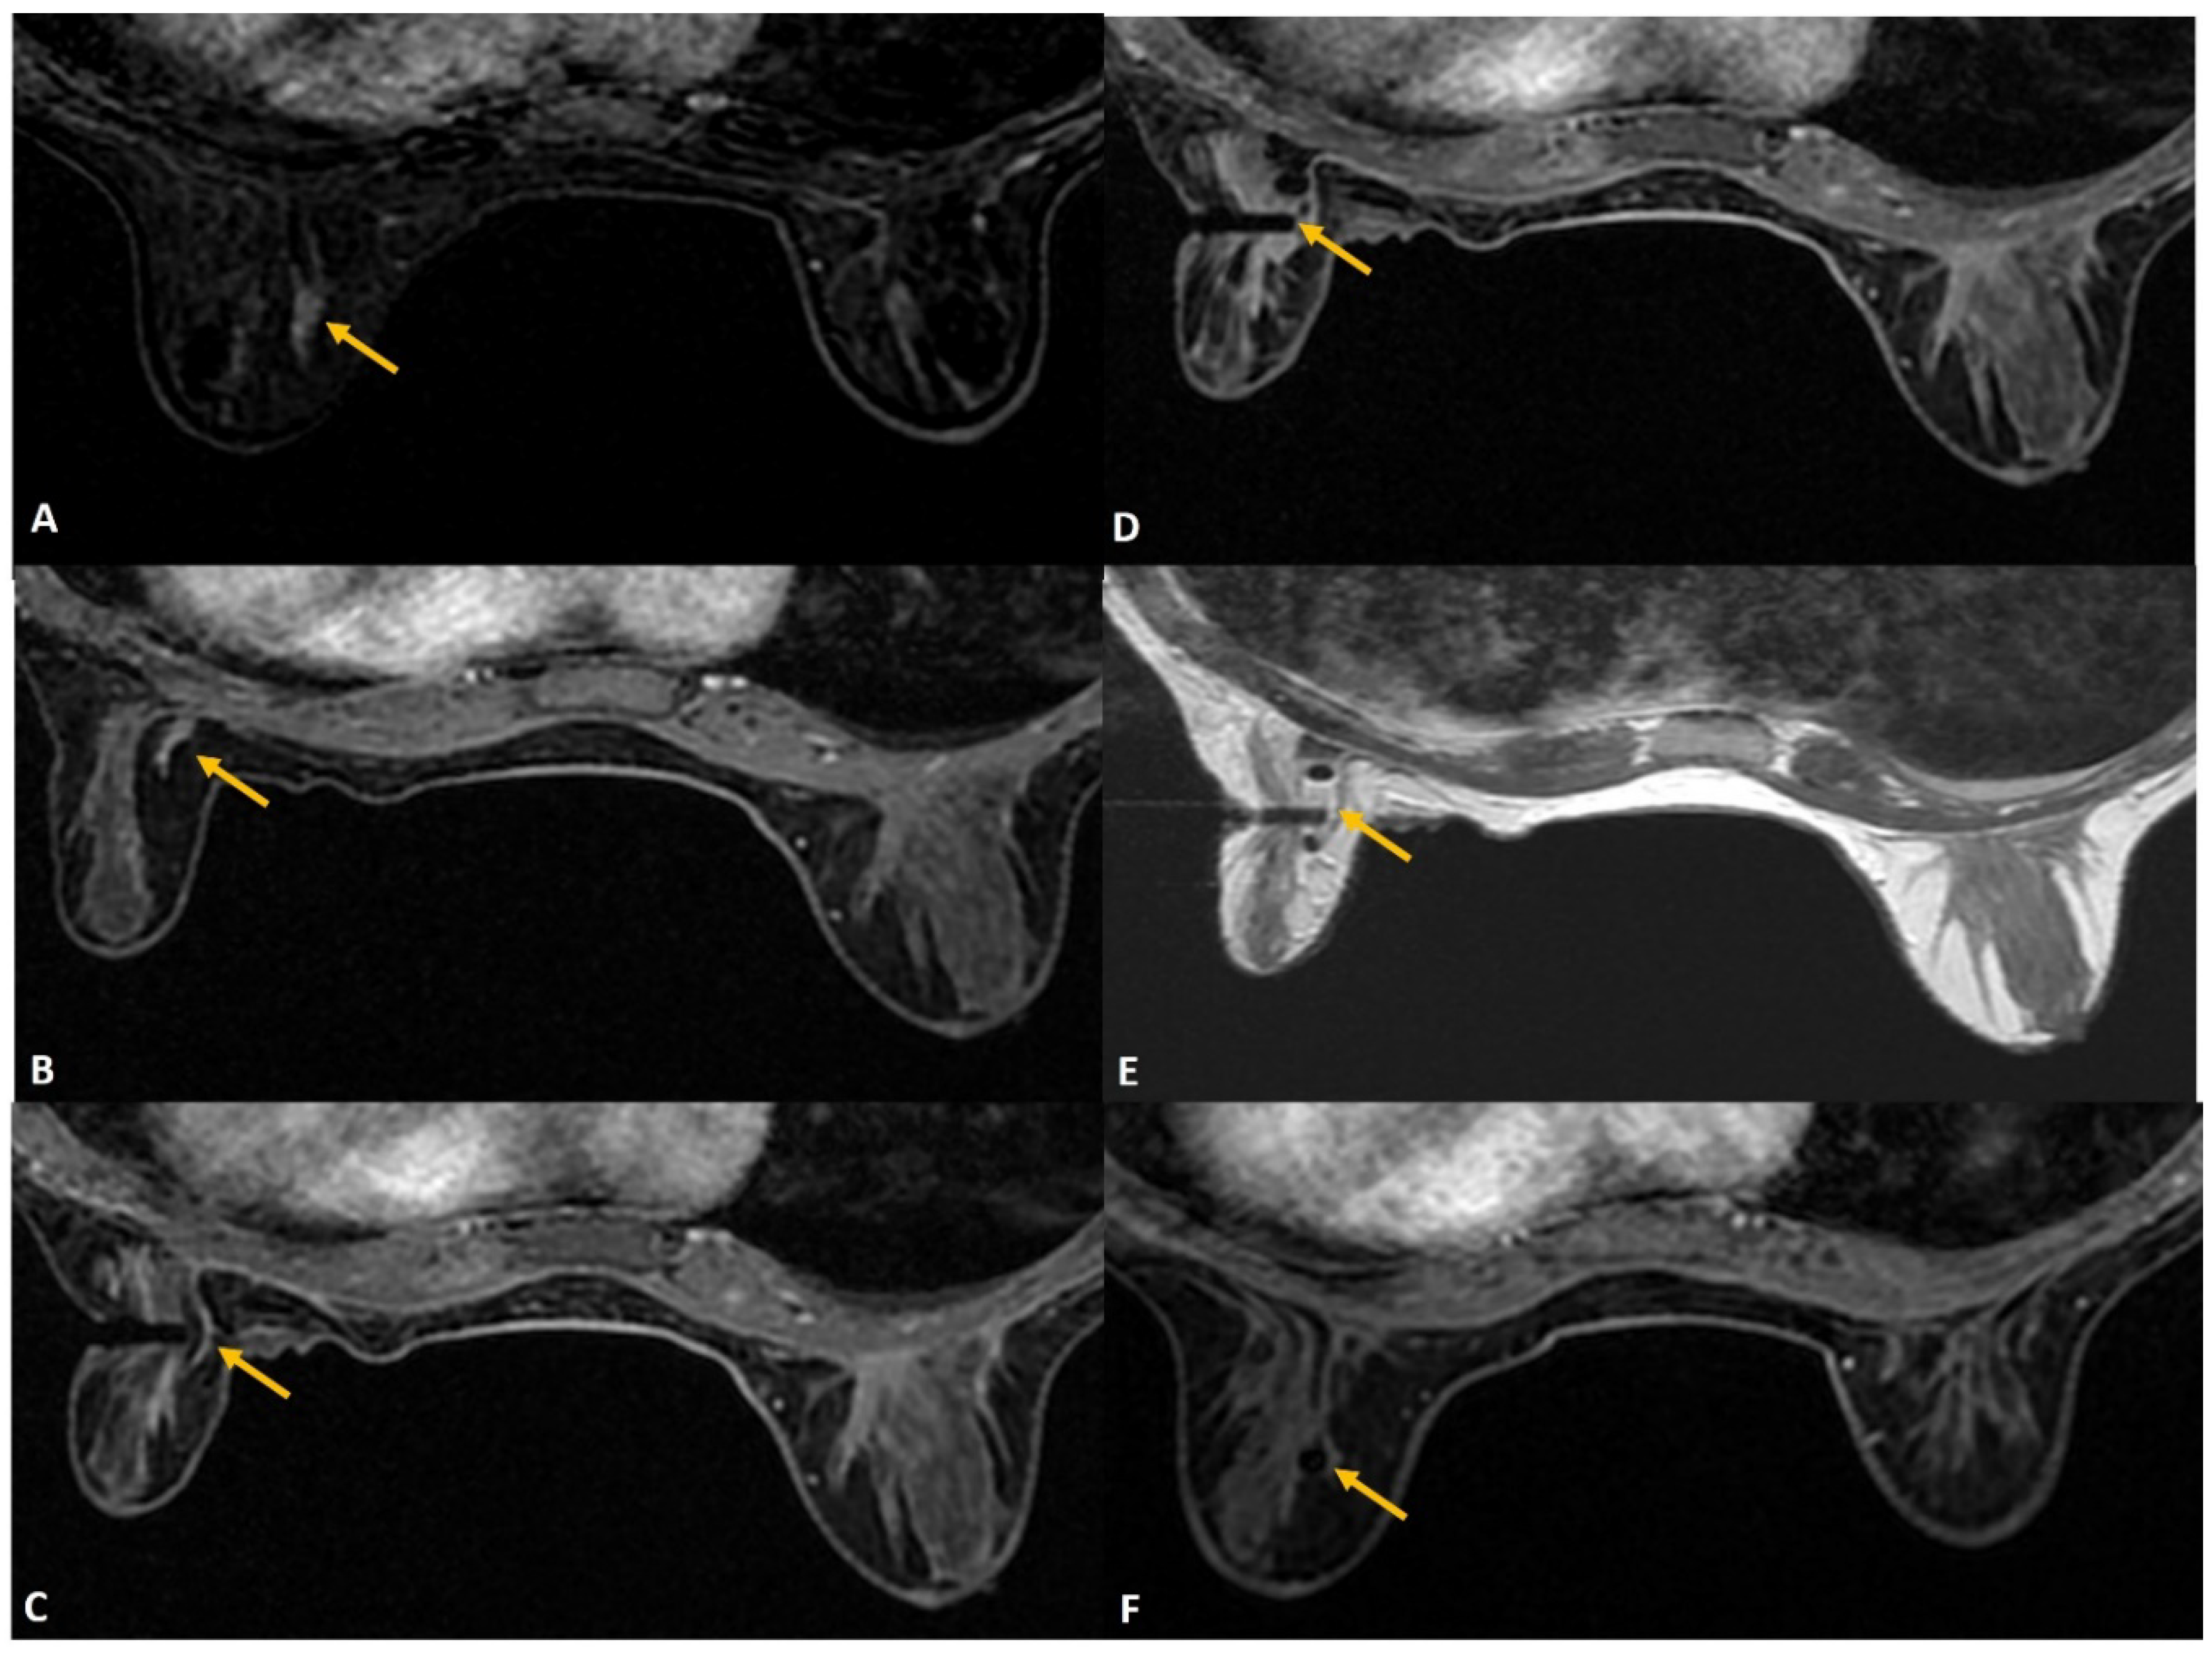

(A). Screening MRI in a high-risk patient showed a new indeterminate focal non-mass enhancement (yellow arrow) in left breast. (B). During the biopsy, the enhancing lesion (yellow arrow) was seen compressed and pushed along posterior aspect. (C). The lesion (yellow arrow) was displaced medially by the obturator of the biopsy guide. (D). The needle was pushed beyond the target and then withdrawn to correct depth (yellow arrow). This strategy helped to place the needle well in relation to the target lesion. (E). Post-biopsy hematoma (yellow arrow) is noted. (F). Follow up MRI after a year confirmed appropriate location of the marker clip with lack of enhancement in this region (yellow arrow). The histology of this lesion was reported as sclerosing adenosis.

Figure 8.